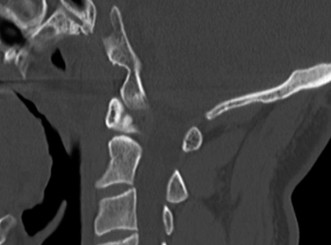

Initial trauma radiographs demonstrated a loss of anterior and middle column height at L1, with a focal kyphotic deformity. However, plain films are vastly insufficient for definitive surgical planning in thoracolumbar trauma. A high-resolution, fine-cut Computed Tomography (CT) scan of the entire spine was obtained. The CT images confirmed an L1 burst fracture with severe comminution of the vertebral body. Sagittal and axial reconstructions revealed 50% canal compromise secondary to a large retropulsed bone fragment originating from the posterosuperior aspect of the L1 vertebral body. Furthermore, the CT demonstrated 25 degrees of segmental kyphosis measured from the superior endplate of T12 to the inferior endplate of L1.

The MRI, particularly the Short Tau Inversion Recovery (STIR) and T2-weighted sagittal sequences, provided the definitive diagnosis. The images demonstrated profound hyperintensity and discontinuity of the ligamentum flavum, the interspinous ligaments, and the supraspinous ligaments at the T12-L1 level. The facet joint capsules were also disrupted, indicated by fluid within the joints. This complete failure of the PLC means the posterior tension band is gone. Regardless of the bony parameters, this spine cannot resist physiological flexion loads. If treated non-operatively, this injury will inevitably lead to progressive kyphosis, delayed neurological deficit, and intractable pain.

Therefore, the gold standard, definitive treatment for this specific injury pattern is an instrumented posterior fusion. By placing pedicle screws above and below the fractured level, we can utilize ligamentotaxis to partially reduce the retropulsed fragment, restore vertebral height, and rigidly recreate the posterior tension band. This is where the concept of preventing Adjacent Segment Degeneration (ASD) enters our operative planning. If we fuse this patient in 25 degrees of segmental kyphosis, we will create a flatback deformity. The adjacent unfused segments (particularly L2-L3 and L3-L4) will be forced into hyperlordosis to compensate, leading to accelerated facet arthropathy, disc degeneration, and eventual adjacent segment failure. Our surgical goal is not just stabilization, but the meticulous restoration of regional sagittal alignment.